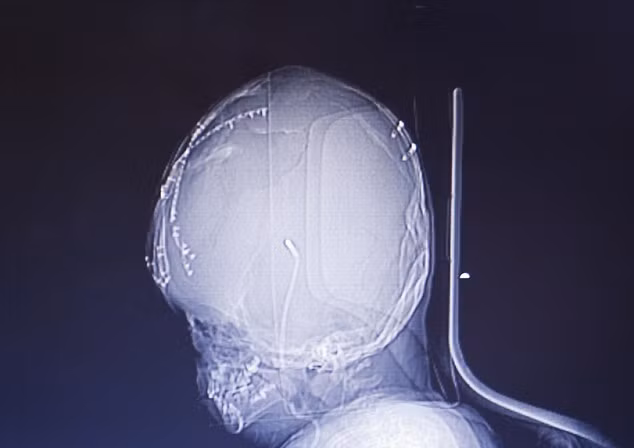

Roona Begum (3 tuổi) ở Ấn Độ bị mắc bệnh úng thủy não khiến đầu của em tăng lên gấp 3 lần bình thường. Roona Begum đã được đưa tới bệnh viện ở New Delhi, Ấn Độ, năm ngoái.

Các bác sĩ đã tiến hành một loạt các ca phẫu thuật để giảm kích thước đầu của Roona, tuy nhiên không mang lại nhiều thành công như mong đợi.

Các bác sĩ hầu như đã bó tay và trả bé về nhà với cảnh báo bé còn rất ít cơ hội để sống sót.

Tuy nhiên, chỉ mới gần đây 1 tuần, các nhân viên y tế đã bị sốc khi thấy rằng Roona không chỉ còn sống, cô bé còn bắt đầu giao tiếp và mỉm cười với bố mẹ.

Các bác sĩ cho rằng đây là điều kỳ diệu, bởi hiện tại Roona thậm chí còn có thể giữ đầu thẳng và tự quay từ bên này sang bên kia.

Tuy cô bé đang phục hồi với một tốc độ đáng ngạc nhiên nhưng với việc hộp sọ bị biến dạng do não úng thủy, bộ não của Roona chắc chắn sẽ chịu nhiều thiệt hại. Câu chuyện của Roona đã gây xúc động cho các bác sĩ và các tổ chức y tế, từ thiện. Hiện cô bé đã được điều trị miễn phí.